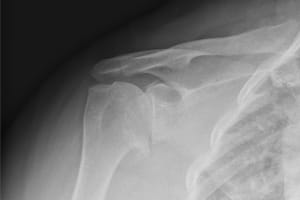

BEFORE:

This is an x-ray before surgery demonstrating end stage "bone on bone" arthritis of the shoulder.